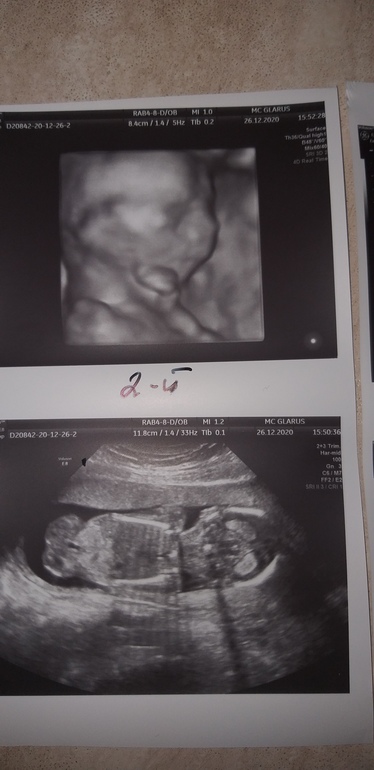

УЗИ 16-17 недель Ди-Ди + фото

Первый вес 165, Чсс 156 идет по сроку, пол,Мальчик💙 Плацента по передней стенке матки и в дне, толщина 17мм.

Второй, вес 155, Чсс 145 идет по сроку, пол,Мальчик💙 Плацента по передней стенке, толщина 15мм,нижний край на 20мм выше внутреннего звена.